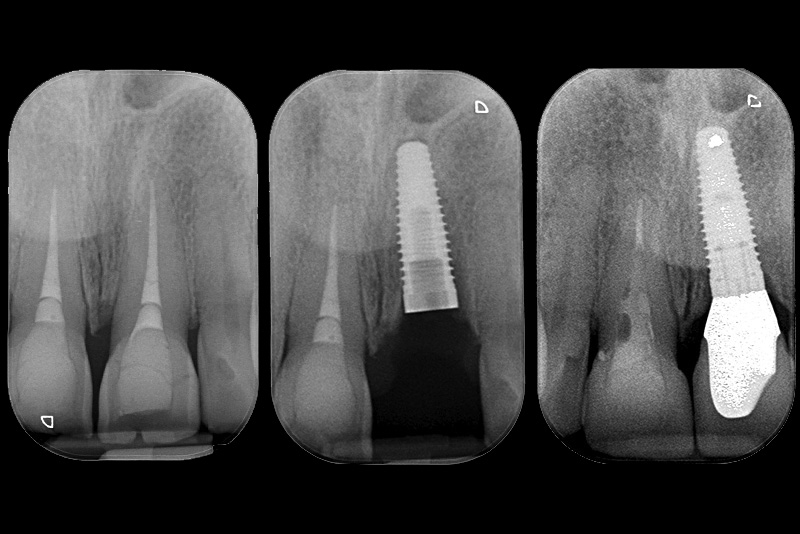

PREMESSA: in seguito all’estrazione dell’incisivo laterale superiore di destra, resasi necessaria per cause batteriche, si decide di affrontare il caso con il posizionamento di un impianto in sostituzione dell’elemento mancante dopo guarigione del sito infetto. Con tecniche rigenerative sia dei tessuti ossei mancanti a causa dell’infezione pregressa, sia dei tessuti gengivali che appaiono inizialmente troppo spostati in alto, si ripristina una corretta morfologia delle parabole (contorni) gengivali e delle papille interdentali (triangoli di gengiva tra due denti vicini).

Vengono utilizzati 2 tipi di provvisori: il primo, cementato ai denti vicini, viene utilizzato dal momento dell’estrazione del dente fino ad impianto osteointegrato (circa 6 mesi); il secondo, avvitato direttamente all’impianto, ha una funzione di prova estetica ma soprattutto di guida per la maturazione dei tessuti gengivali peri-implantari portandoli verso la maturazione completa prima di posizionare la corona finale in disilicato di litio.